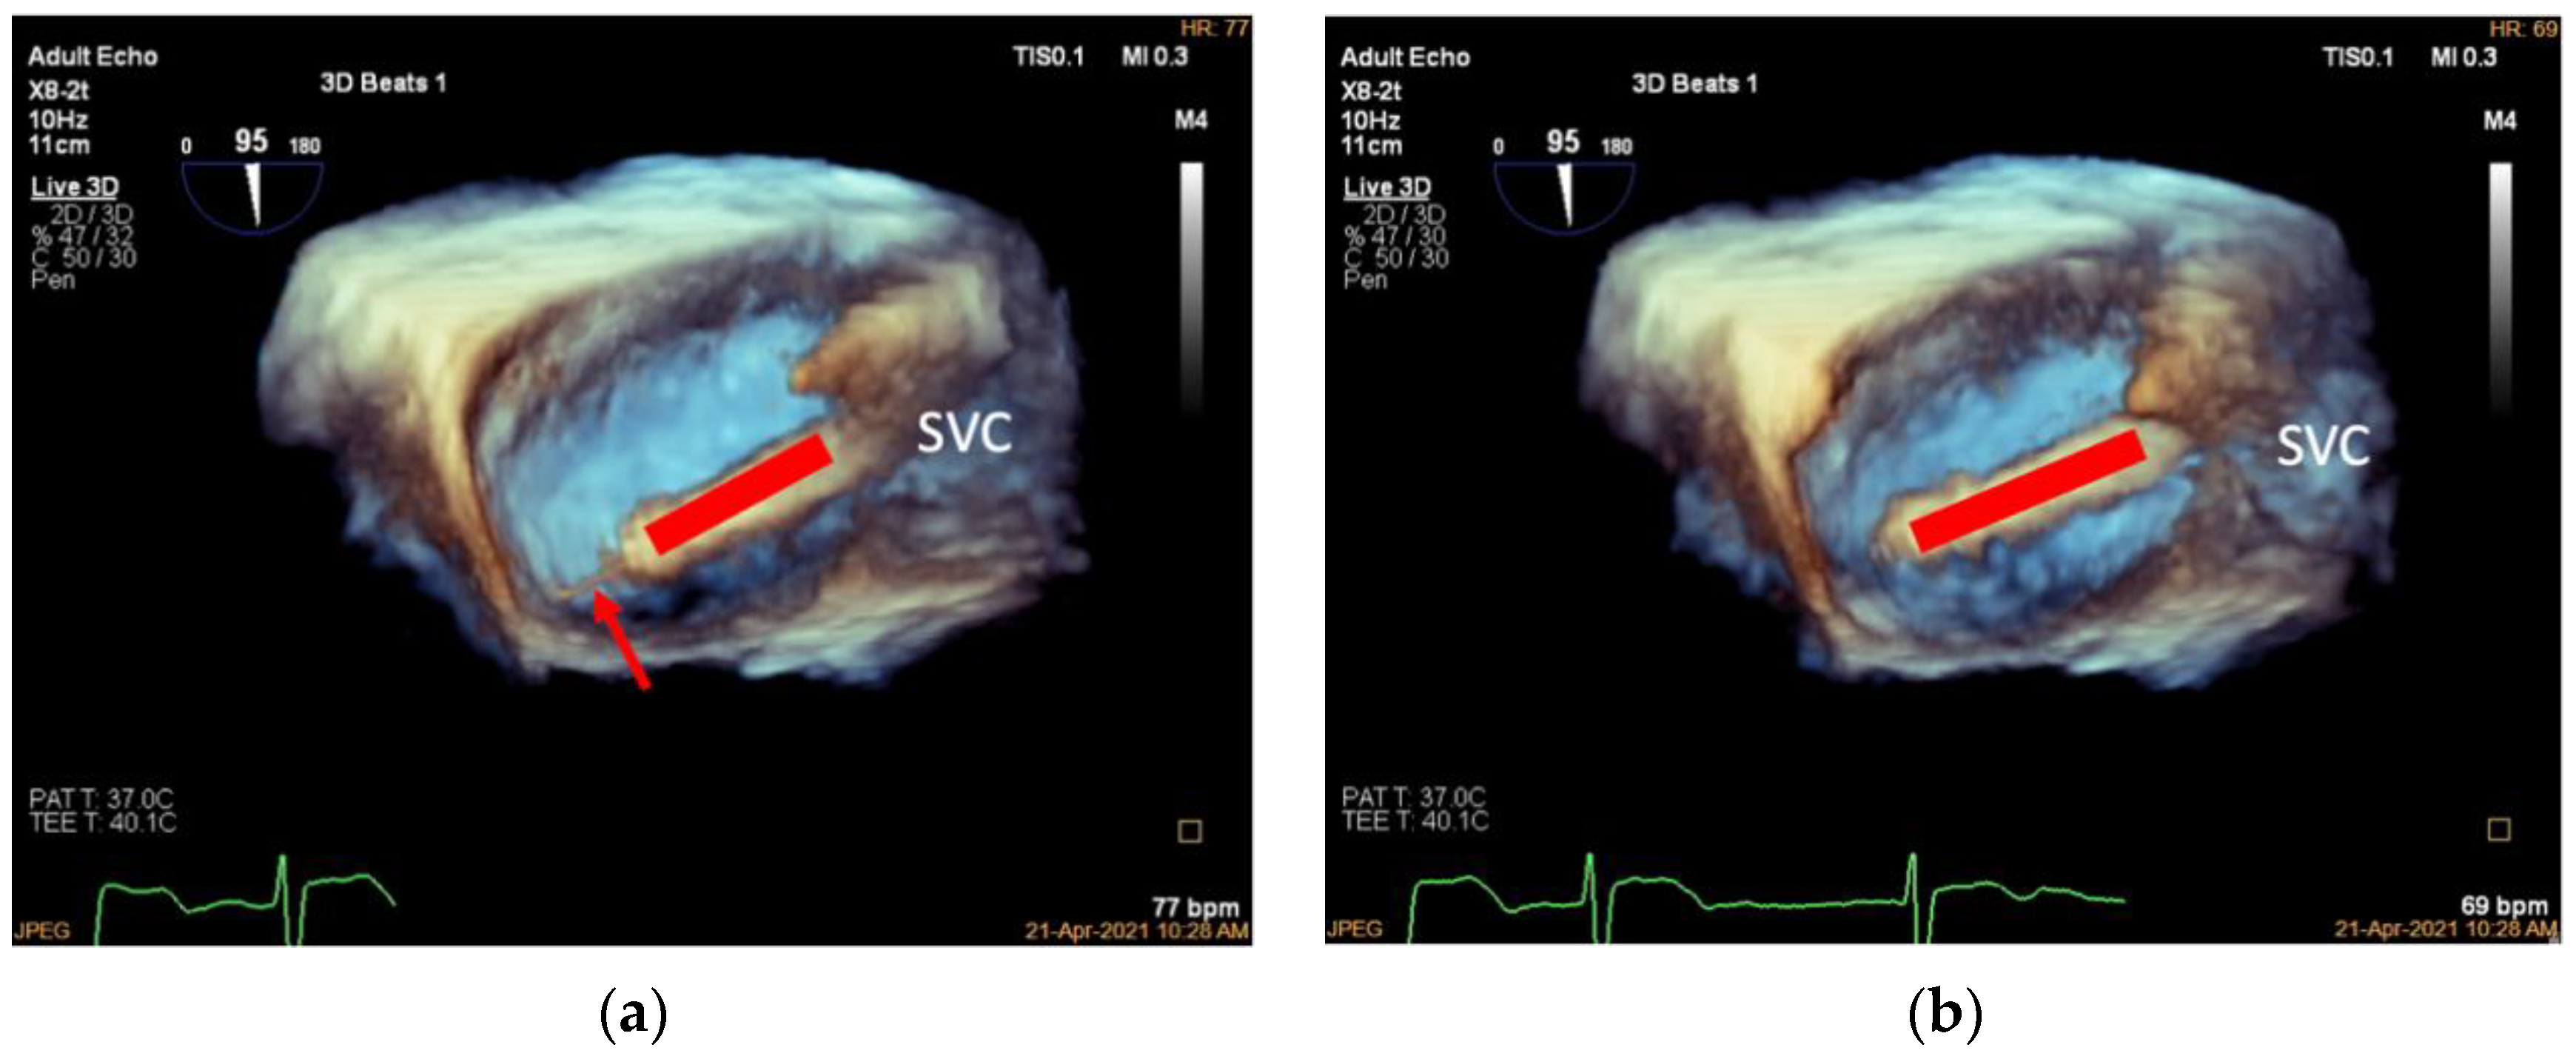

3.3. Deployment of the Tapping Screw-Shaped Anchor

| Step 2. Deployment of the tapping screw-shaped anchor | X-plane view with ME RV inflow–outflow view as the primary view | about 60° | Deployment of the tapping screw-shaped anchor should always be monitored under 2D TEE |

| 3D TV en face view | about 60° | Further confirmation of the target annular location | |